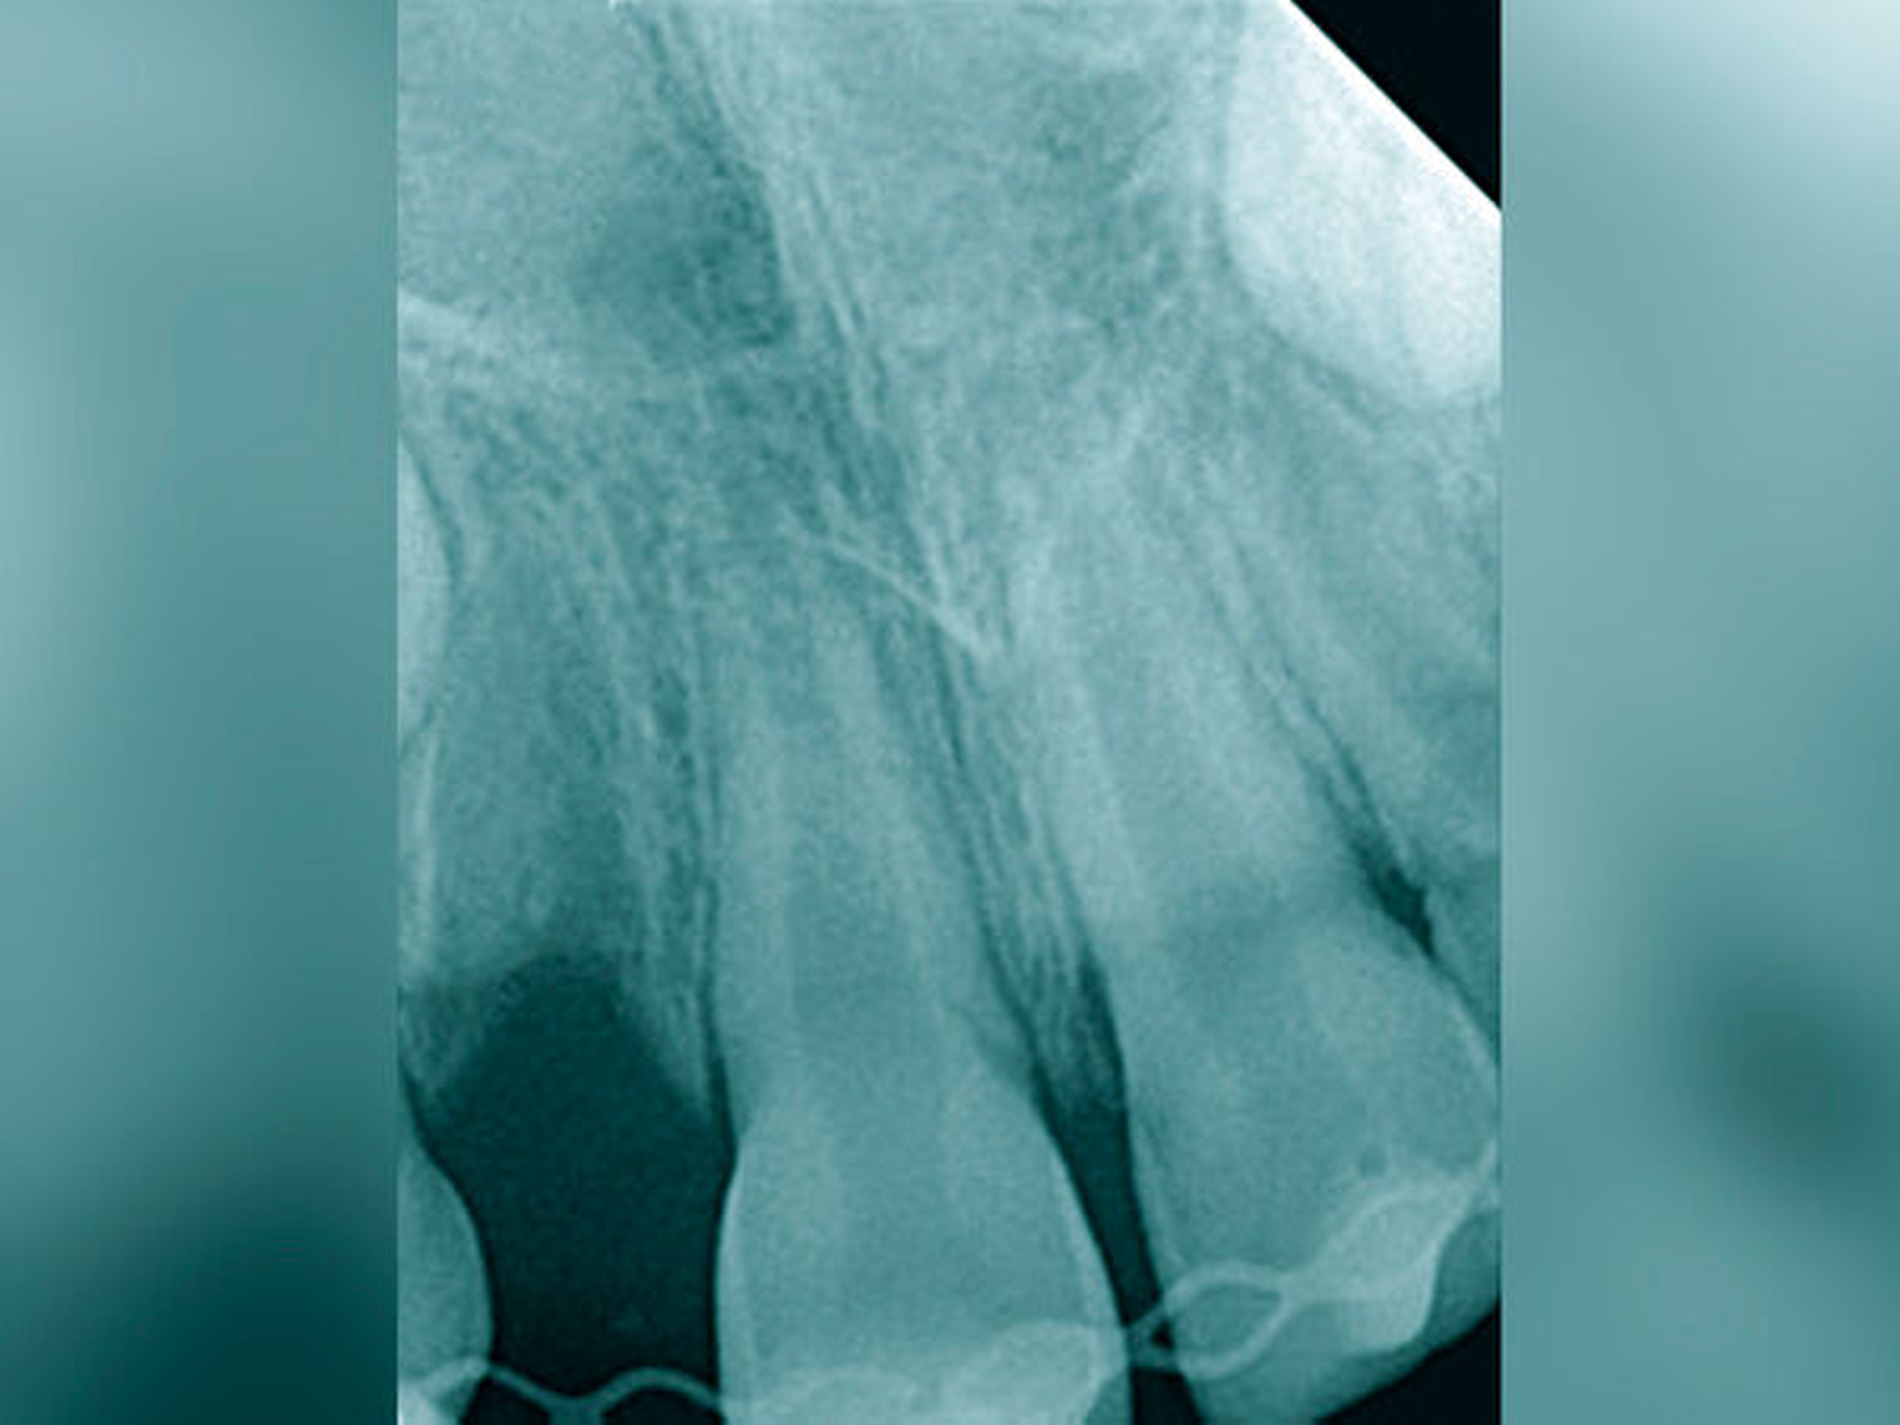

Die Häufigkeit für den Frontzahnverlust beträgt drei bis vier Prozent. Die Altersgipfel liegen zwischen dem achten und dem neunten sowie vom zwölften bis zum 14. Lebensjahr. Betroffene Zähne sind der mittlere und der seitliche Schneidezahn im Oberkiefer. Es besteht eine Korrelation der Häufigkeit zu den Zahnstellungsanomalien der vergrößerten sagittalen Schneidekantenstufe, dem schmalen Deckbiss mit protrudierten seitlichen Schneidezähnen und progen stehenden Einzelzähnen. Obwohl bei Avulsion die sofortige Reimplantation zum Erhalt des Zahnes führen kann, sind häufig Ankylosen des Parodonts und Wurzelresorptionen mit begrenzter Erhaltungswürdigkeit die Folgen. Eine fehlende Sensibilität, ein hoher Klopfschall und der röntgenologische Resorptionsnachweis sind diagnostische Anzeichen dafür.